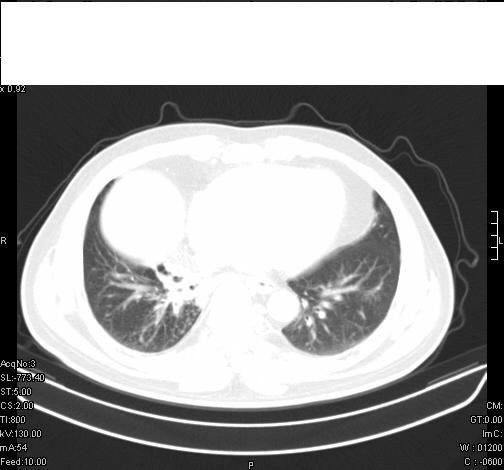

前几天,发了患者的平扫片,患者抗炎一周后增强扫描。右中叶病灶吸收明显,但下叶病灶未见明显吸收。右肺门可见结节影,看来凶多吉少

右肺下叶支气管管腔狭窄,管壁增厚,右下肺见斑片状高密度影,考虑右侧肺门中心肺癌伴阻塞性肺炎

右肺下叶散在的斑片状致密影,下叶支气管变窄。考虑:右肺慢性炎症。

第18幅,好像不能简单用炎症解释,前几天我发平扫时,90%人支持肺癌,现在好像大家更倾向于炎症了,我觉得还是不能排除肺癌。

右肺下叶支气管壁明显增厚,考虑癌症并阻塞性炎症、肺门淋巴结肿大

考虑右肺癌并阻塞性炎症、肺门淋巴结肿大

右肺下叶支气管壁不规则增厚,右肺下叶有斑片状影分布。考虑右肺中央型肺癌伴右肺下叶阻塞性改变。建议支纤镜检查。平扫比增强较好显示了病变情况。

右主支气管狭窄,管壁增厚。考虑右中心性肺ca伴阻塞性肺炎。

既然抗炎治疗有效,可继续治疗;右肺下叶支气管管腔狭窄,管壁增厚,右下肺见斑片状高密度影,右侧主支气管后见结节影(淋巴结?),肺癌不能排出。